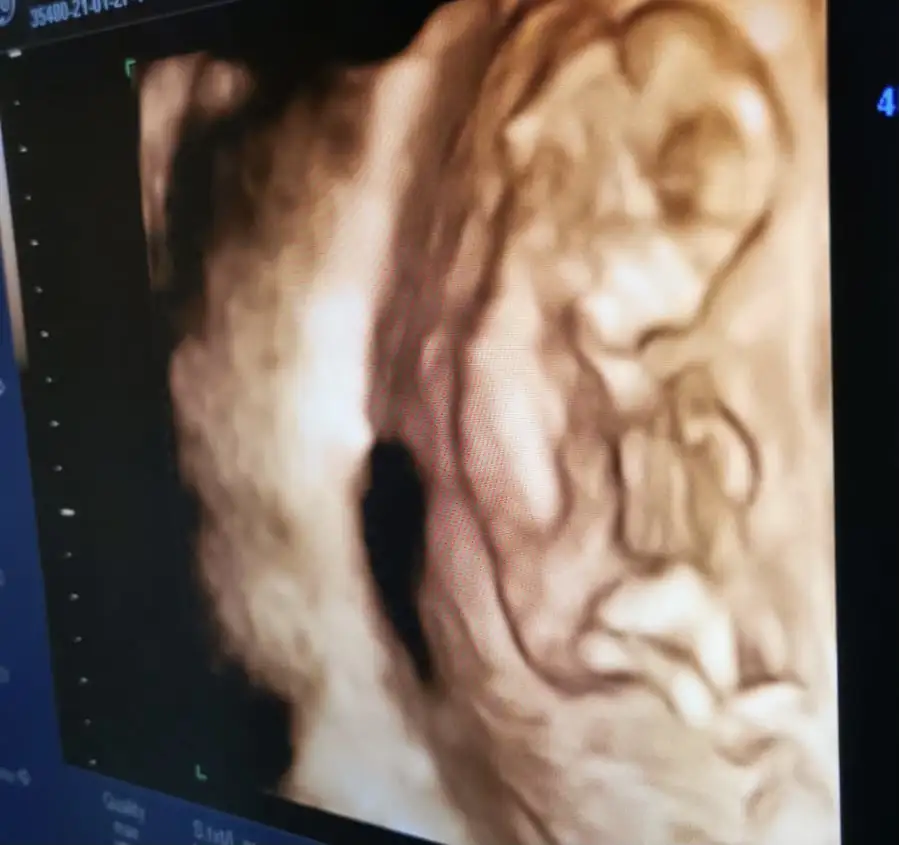

Benim bebeğim de 8 haftalık burada plasenta sağda gibi geldi. Ama yorumlayamadim.. yorumlarınızı bekliyorum ramzi teorisi ileBen neden resim paylaşamıyorum

Bu arada üstten ultrasondur. 8 haftalık ben plasentayi sağda gördüm. Yanlış görmedim isem tabi ama yorumlayamadim... Yorumlarınızı bekliyorum...Benim bebeğim de 8 haftalık burada plasenta sağda gibi geldi. Ama yorumlayamadim.. yorumlarınızı bekliyorum ramzi teorisi ile

Plasenta solda gibiBenim bebeğim de 8 haftalık burada plasenta sağda gibi geldi. Ama yorumlayamadim.. yorumlarınızı bekliyorum ramzi teorisi ile